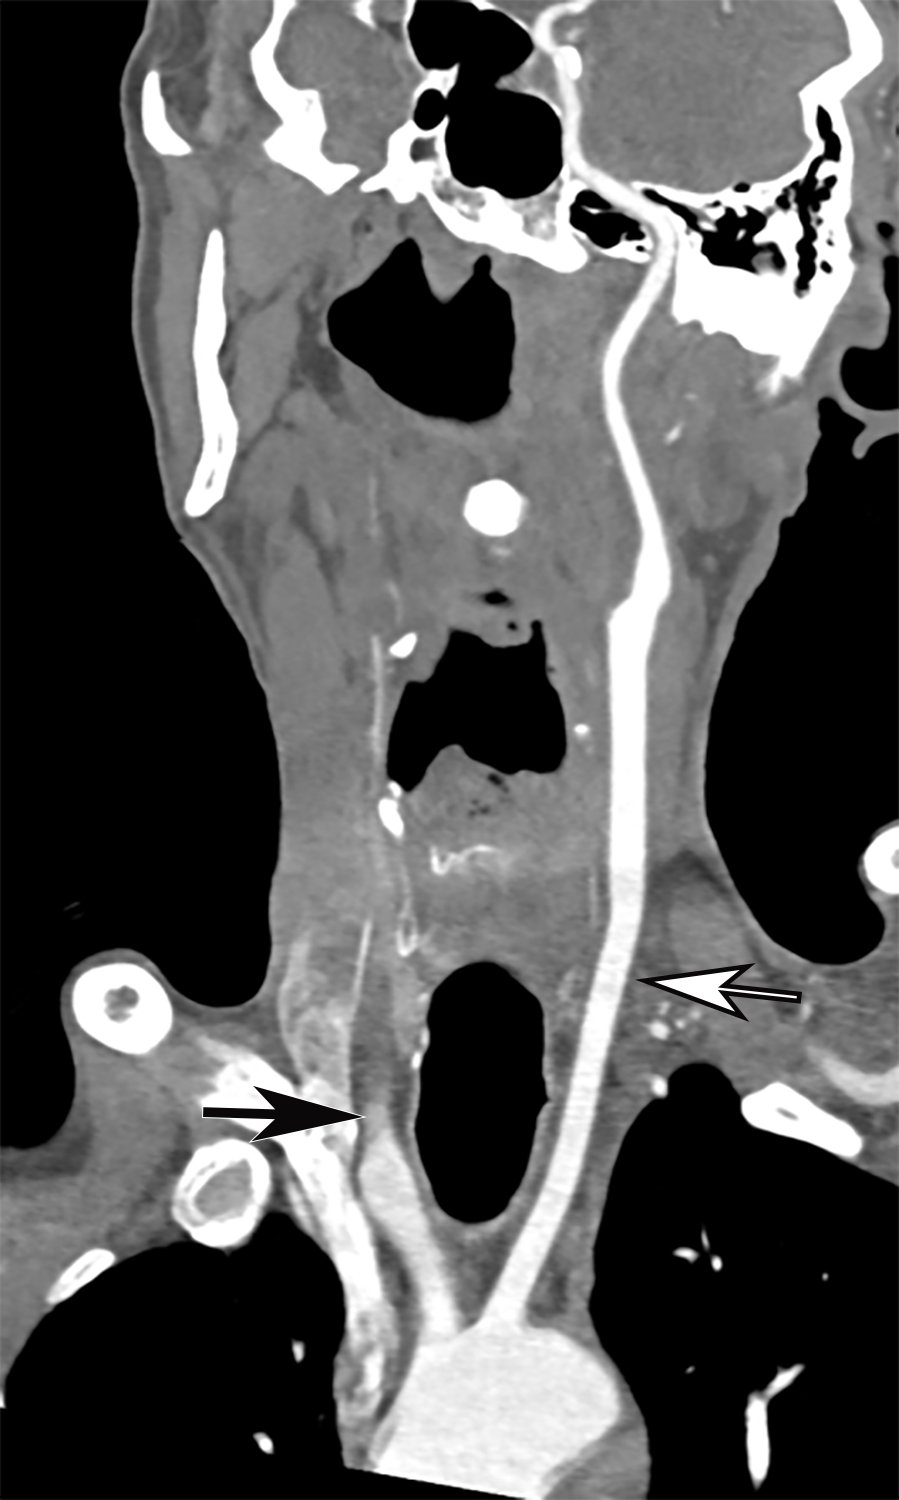

This photo gallery shows the variety of radiological presentations of COVID-19 (SARS-CoV-2) in medical imaging, including computed tomography (CT), radiograph X-rays, ultrasound, echocardiograms and magnetic resonance imaging (MRI). The radiology images show examples of typical COVID pneumonia in the lungs and the numerous complications the virus causes in the body in multiple organs, including the brain, kidneys, heart, abdomen and vascular system.

Ultrasound, especially hand-held ultrasound imaging devices, have become a primary imaging modality for novel coronavirus because of the ease to bag the device and sterilize it after use. CT and mobile X-ray systems are also used as front-line imaging systems for COVID-positive or suspected COVID patients.

The images were collected from physicians, study authors, universities and hospitals, the National Institutes of Health (NIH), the Radiological Society of North America (RSNA), the American College of Radiology (ACR), Centers for Disease Control and Prevention (CDC) and radiology technology vendors.